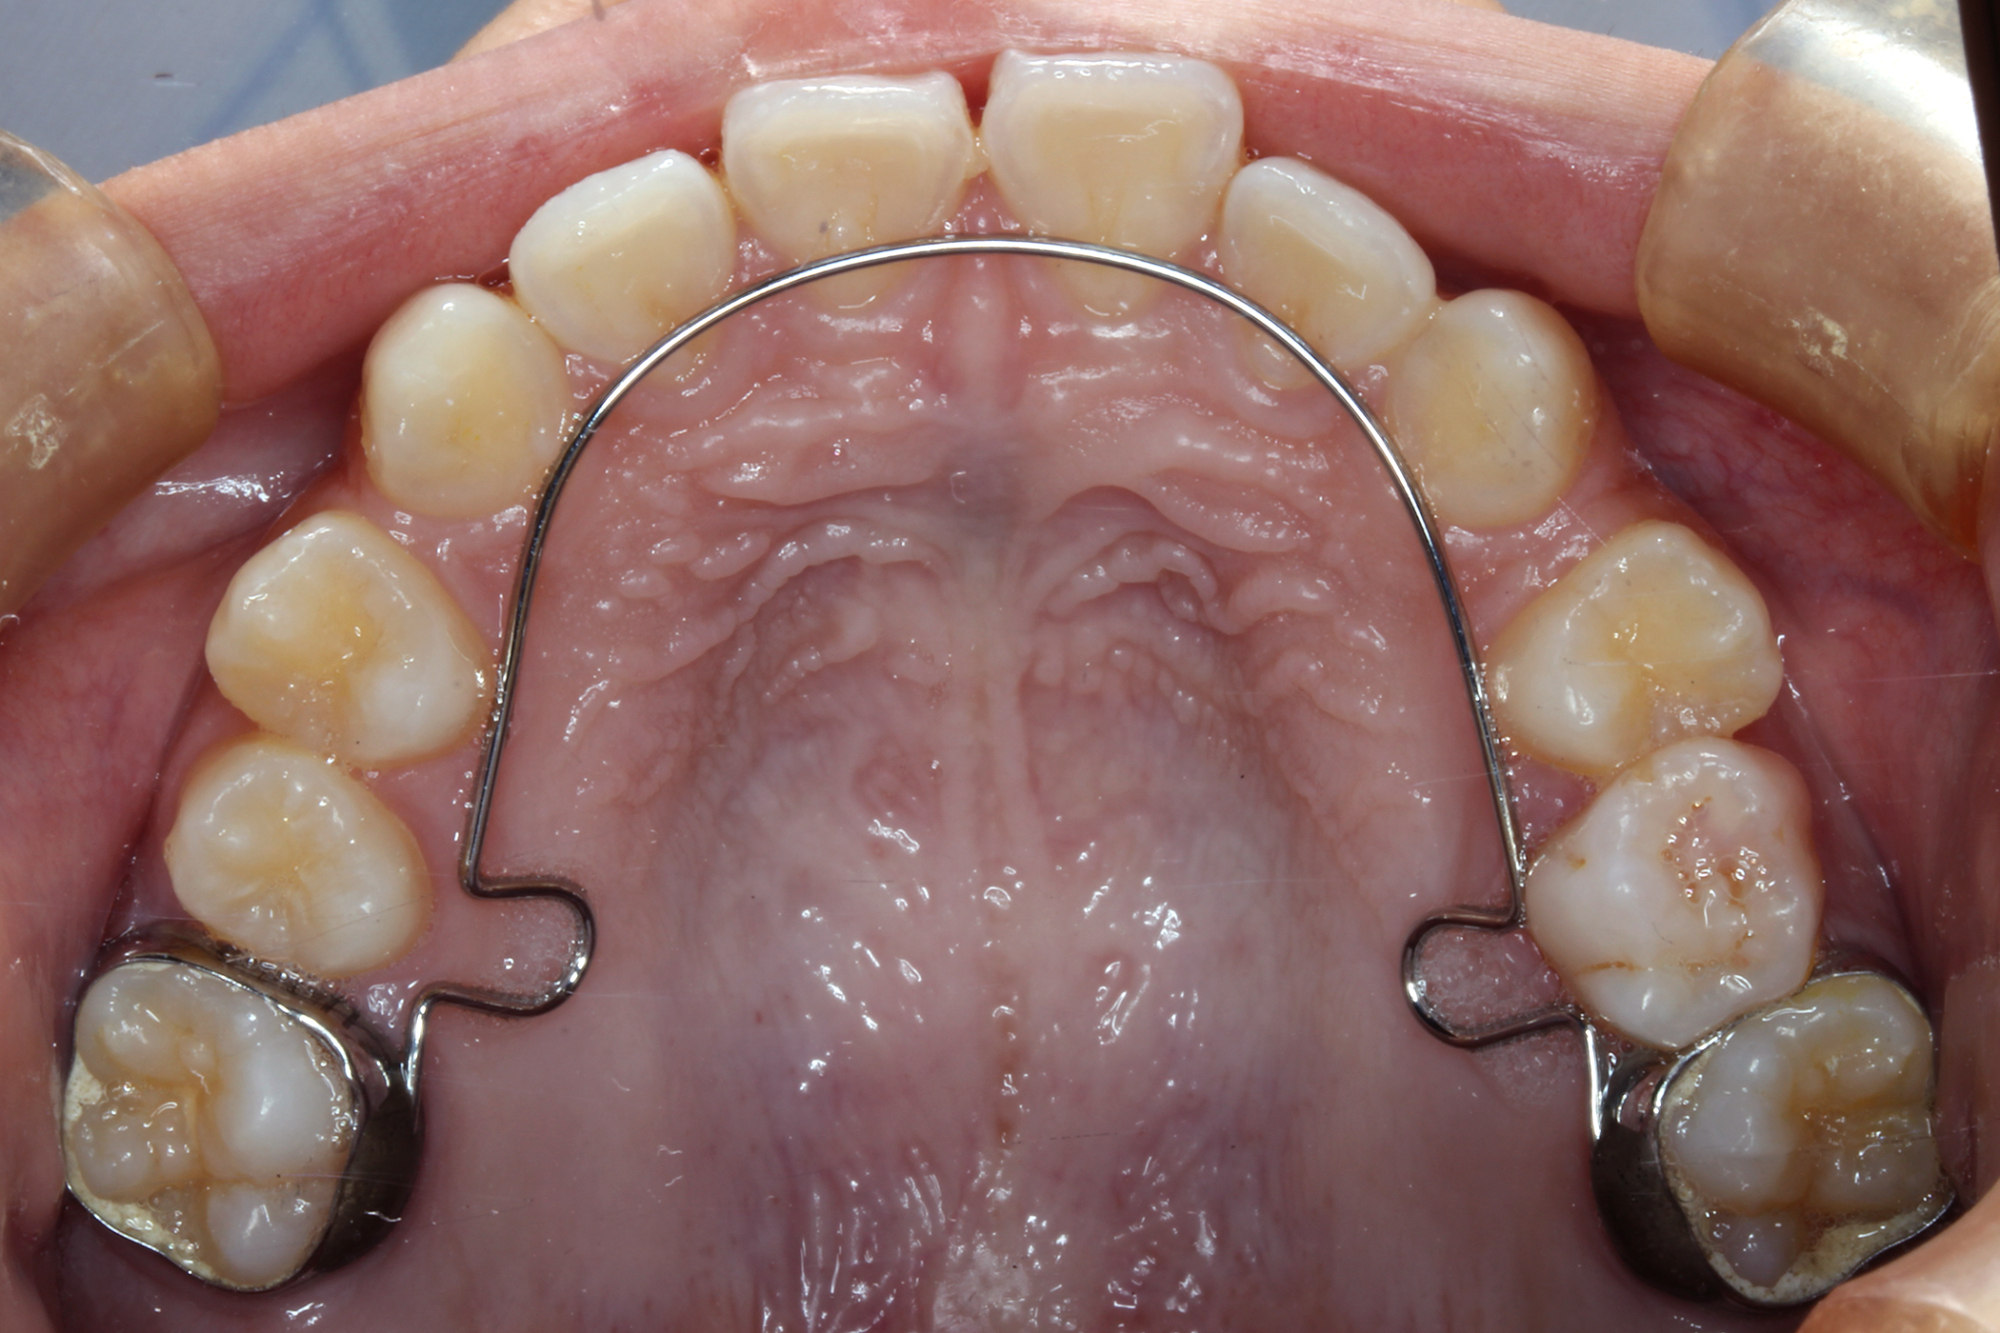

日本で行われている拡大床治療にも色々な方法がありますが当院での特長は最初に永久歯に生え替わる上下4本の前歯を奥歯の生え替わりが始まる前までに顎を拡大してきれいに並べることです。そのため拡大床治療の期間は小学校1年生頃から4、5年生頃までの間に限定しており、それまでに目的が達成できない場合には別の治療法に移行します。またゆっくりスペースを獲得するようにしているのも特長で2週間に1回ネジを回すようにしています。一般的には1週間にⅠ回ないし2回ネジを回すことが多いようです。ゆっくり進めるので一日の装着時間はお家にいるときと寝ている間だけにしています。学校や自宅以外での装着はせずゆっくり拡大していくので治療期間が長くなりますが後戻りは少なく確実になります。治療開始時期が大切ですので時期を逸した場合には拡大床治療は行いません。一般的に拡大床治療の評判が悪いのは開始時期が遅く、いつまでも治療を長引かせ治らないことによるものが多いようです。 拡大床治療はスペースを作って永久歯がならぶスペースを作ることが目標ですので細かい歯の向きや角度まで整えられないこともあります。そんな場合には別の矯正治療が必要になります。

拡大床治療で顎のスペースを拡げられるのは11歳くらいまでです。そのため個人差はありますが遅くても小学校2年生までに始めなければなりません。下の前歯が生え替わりはじめた頃から下の前歯が4本、上の前歯が2本生え替わる頃までが始め時です。すでに上下4本とも生え替わってしまった場合にはすでに遅いことが多くあります。